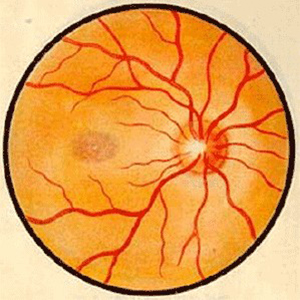

视神经病变

宜昌太阳成tyc122cc(中国)集团中医眼科主任秦大军接连为视神经病变患者医治